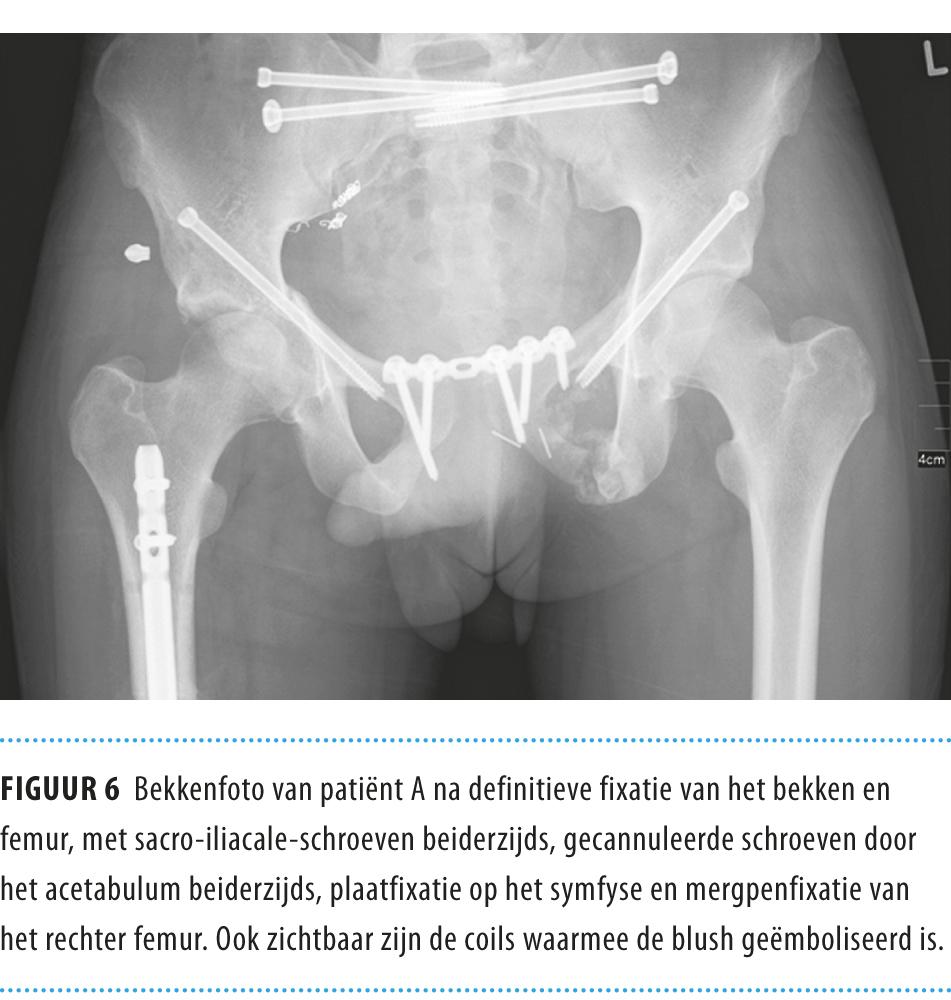

Hierna stabiliseerde de situatie en kon patiënt naar de intensive care worden overgebracht. Na 24 h verrichtten we een relaparotomie om de gazen te verwijderen en een dunne-darmanastomose aan te leggen. 48 h na binnenkomst op de SEH vond de definitieve operatie aan het bekken plaats, waarbij we beiderzijds computergenavigeerd 2 SI-schroeven plaatsten met tevens gecannuleerde schroeven over het acetabulum beiderzijds. In diezelfde operatie voltooiden we de behandeling van de femurfractuur met een mergpenfixatie (figuur 6).

Figuur 6